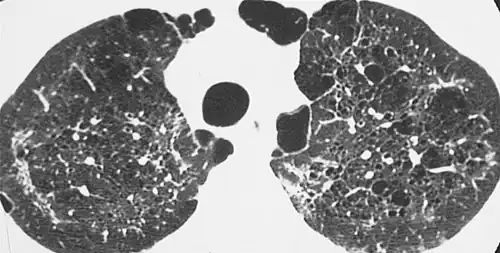

| CT scan of the lung showing bullae in the lower lung lobes of a subject with type alpha-1-antitrypsin deficiency. There is also increased lung density in areas with compression of lung tissue by the bullae. | |

- Alpha 1-antitrypsin deficiency[6]